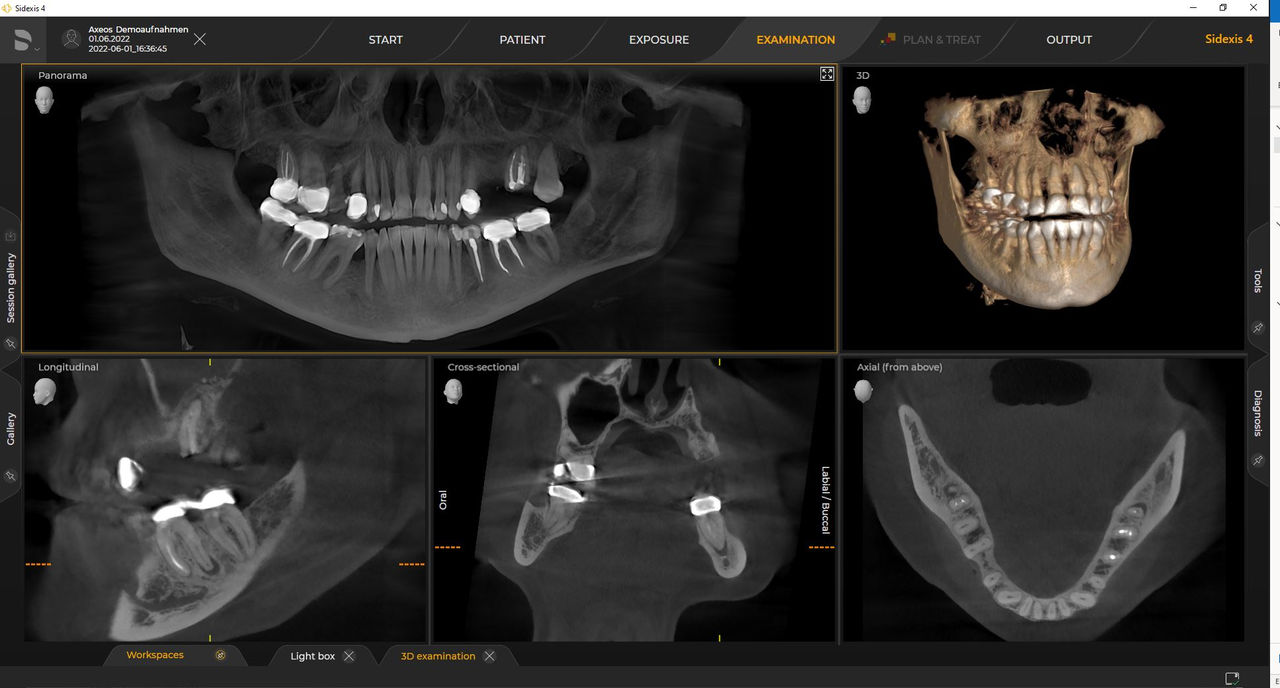

Axeos, el sistema especializado 2D/3D con un gran volumen y alta calidad de imagen para clínicas con una amplia oferta de tratamientos. Desarrollado junto a dentistas y clínicos, Axeos ofrece la gama más completa de funciones de todos los equipos de radiología extraoral de Dentsply Sirona. Además de una excelente calidad de imagen y tamaños de volumen 3D personalizados, el equipo de radiología dental está completamente optimizado para una mayor comodidad del paciente. Axeos no solo proporciona calidad en rendimiento y comodidad, sino también con su galardonado diseño gracias al gabinete integrado para el almacenamiento de posicionadores de mordida y la luz ambiental.

Los requisitos siguen aquellos del software de procesamiento de imágenes de Sidexis 4 y Axeos. Para obtener más detalles, consulte los requisitos del sistema Sidexis 4 y los requisitos de instalación de Axeos.

Las unidades 3D de Dentsply Sirona funcionan exclusivamente con Sidexis 4. Sin embargo, la migración de datos de Sidexis XG a Sidexis 4 es muy fácil. Sidexis 4 permite una experiencia digital completa con las últimas herramientas.